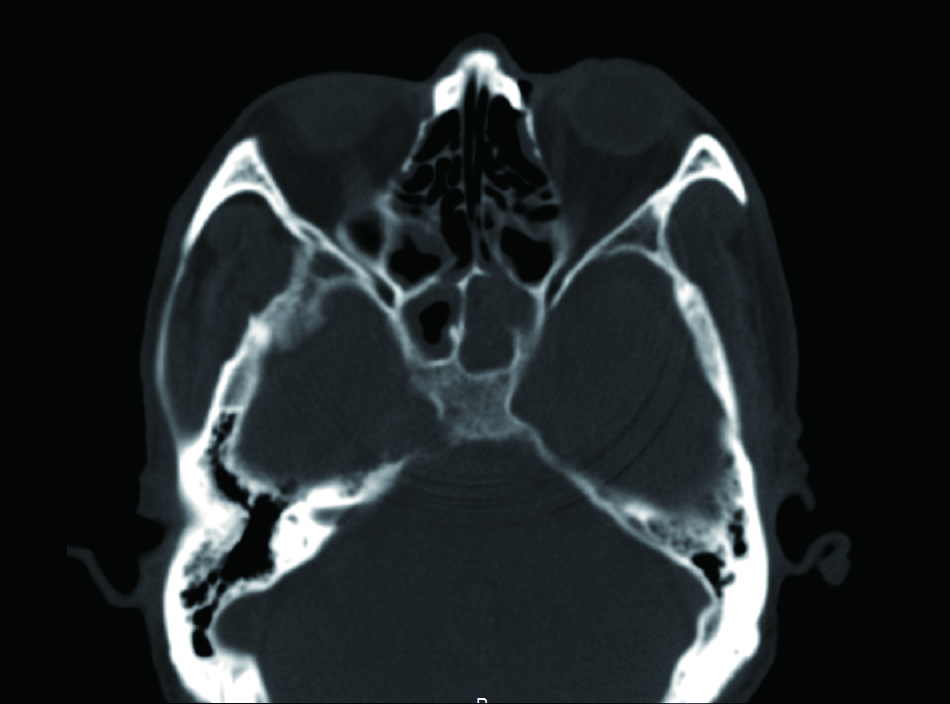

病例1,患者男性,66岁,因头痛3周,复视1周入院。患者3周前起右侧太阳穴针刺样疼痛,影响睡眠。2周前出现咽痛鼻塞流涕及双耳听力下降,伴有右侧额部皮肤红疹,上述症状在当地医院治疗后减轻。1周前出现复视,当地医院治疗后症状无好转,诊断:颅内感染,多颅神经麻痹转来本院急诊。查体:神清,面部可见散在淡色丘疹,以右侧前额为主,右眼外展受限,面部痛触觉无殊,四肢肌力5级,病理反射阴性。脑脊液生化常规示:潘氏试验阳性,有核细胞970/μL;血沉28.00 mm/h,C反应蛋白14.1 mg/L。增强头颅MR提示两侧海绵窦增粗增宽,考虑炎症,并见双侧筛窦上颌窦蝶窦炎(图 1)。予头孢曲松钠2.0 g静脉注射抗感染治疗。治疗2周后头痛明显减轻,但复视症状无好转。复查血常规正常,C反应蛋白正常范围,血沉28.00 mm/h,脑脊液生化及常规正常范围。复查头颅增强MR提示病变范围较前无缩小。鼻窦CT提示双侧蝶窦炎症较前加重(图 2)。建议患者行鼻内镜下蝶窦手术。患者自觉症状减轻拒绝手术,要求出院。出院后在外院继续头孢曲松钠抗感染治疗。治疗10 d后因头痛复视症状无改善,并出现面颊部感觉减退再次入院。入院后查血常规,C反应蛋白正常,血沉28.00 mm/h,脑脊液潘氏试验阳性,细胞数量继续减少至60/μL。继续抗感染治疗。再次头颅MR及鼻窦CT复查提示海绵窦及蝶窦内病变较前范围增大(图 3),经多学科讨论,转本科行视频内镜下双侧蝶窦开放术。术后第三天鼻腔填塞物完全抽除后头痛症状明显缓解,术后6 d出院,头痛症状消失,复视仍存,出院后继续抗感染治疗,定期门诊复诊,术后6个月,复视症状消失。

图 2 左侧蝶窦密度增高影,右侧窦内密度增高影,窦内含气